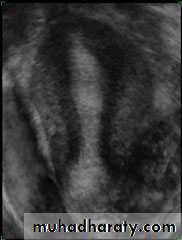

• Intramural leiomyomata are frequently visualized. Examples of fibroids which compromise the contours of the endometrial cavity are shown (A–D). Refraction artifacts resulting from tissue density interfaces and the texture of the fibroids often aid in their identification.Congenital anomalies of uterus

Unicornuate uterusCongenital anomalies of uterus

Bicornuate Bicollis Uterus• Congenital anomalies of uterus

• Didelphic uterus with Left sided hematometra• Congenital anomalies of uterus

• Subseptate Uterus

• Congenital anomalies of uterus

• Complete Septate• Congenital anomalies of uterus

• Arcuate uterusEndometrium